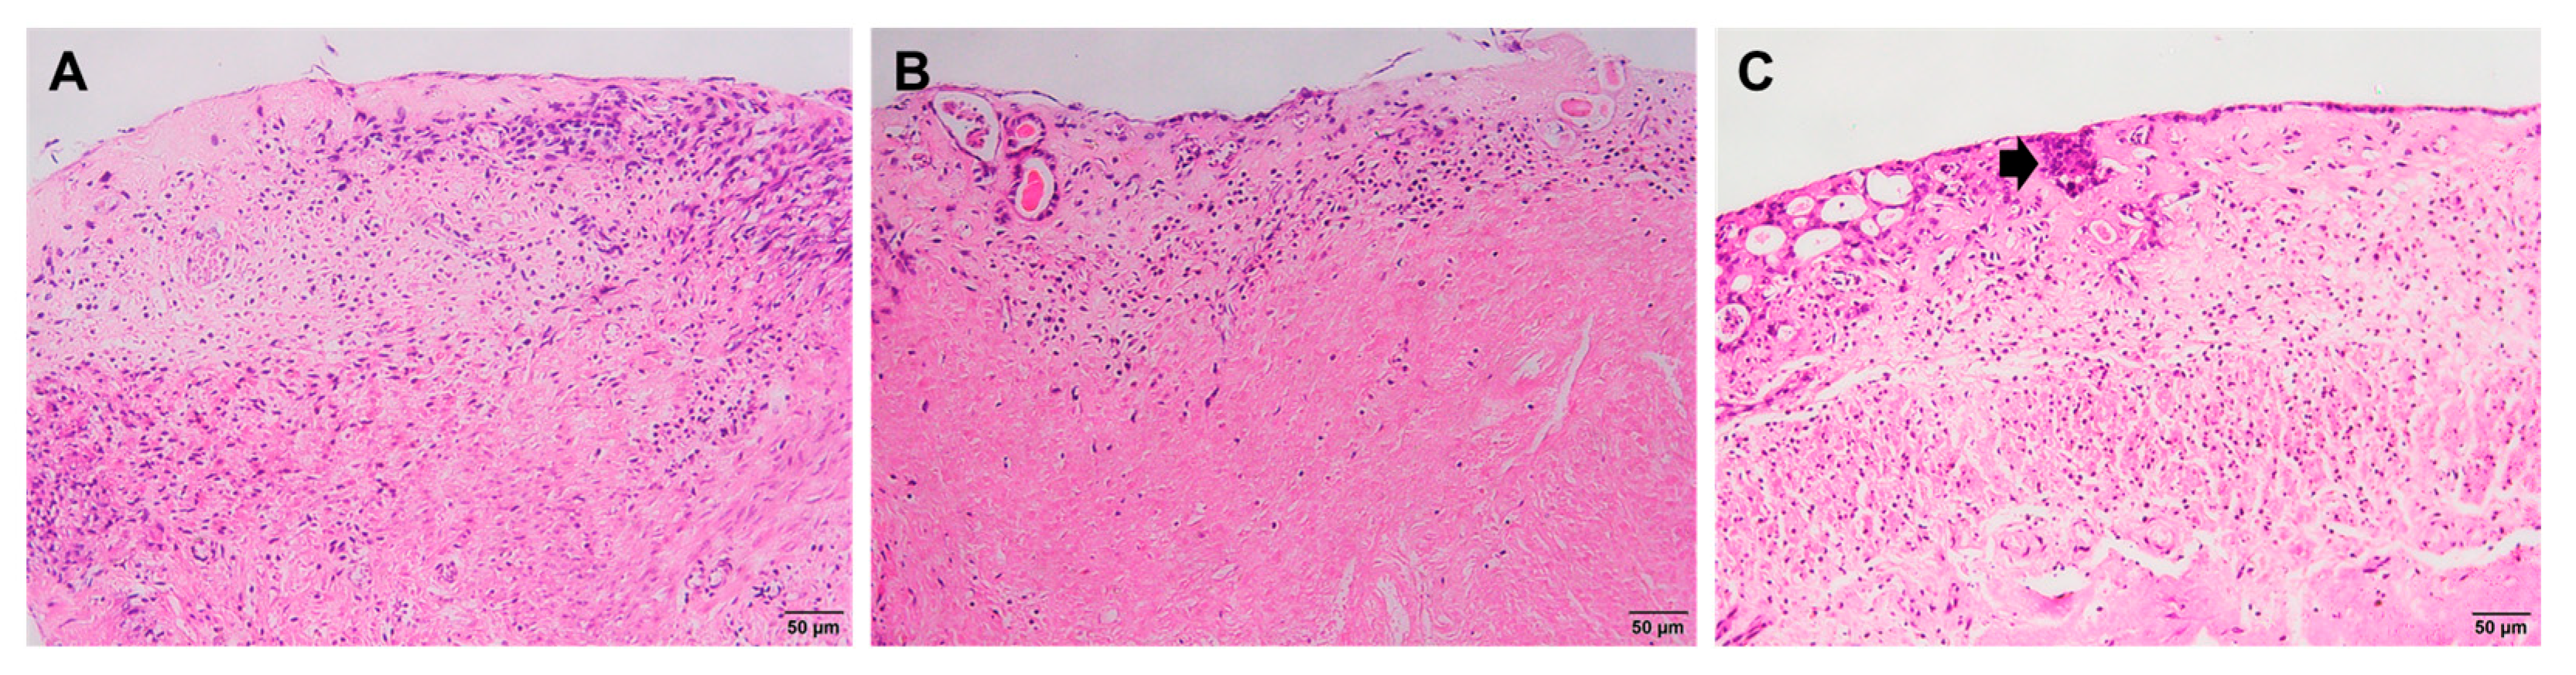

2.2. Histological Staining

| Time | Groups | ||

|---|---|---|---|

| Non-Treated (Control) | PRF Gel-Treated | PRF Lysate-Treated | |

| Day 4 |

|

| |

| Day 8 | |||

| Day 12 | |||

| Day 16 | − Degradation of endometrial tissues (Figure 2(A4,B4,C4)) | ||